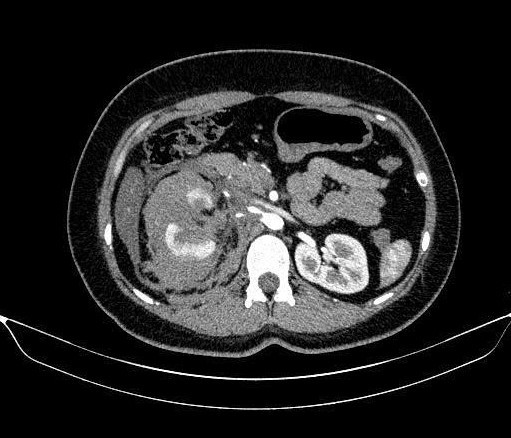

Phối hợp liên chuyên khoa cứu sống bệnh nhân ung thư xương chậu ác tính

Thứ Bẩy, ngày 17/01/2026 07:12Bệnh viện Chấn thương chỉnh hình Thành phố Hồ Chí Minh và Bệnh viện Bình Dân vừa phối hợp liên chuyên khoa trong phẫu thuật thành công cho một trường hợp ung thư...